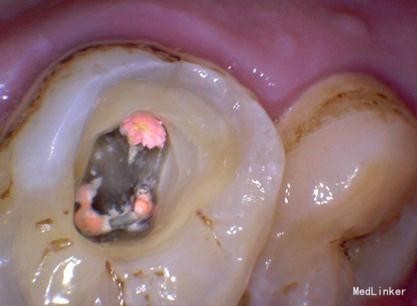

检查:#26 合面见大洞,洞内大量棕黄色腐质,探(++),冷热刺激疼痛加重,扣(—),牙龈未见异常。

诊断:#26牙髓炎 治疗计划:#26根管治疗,后期纤维桩加固嵌体保护冠修复。局部麻醉下开髓,根管预备,消毒。(近中发现mb2)